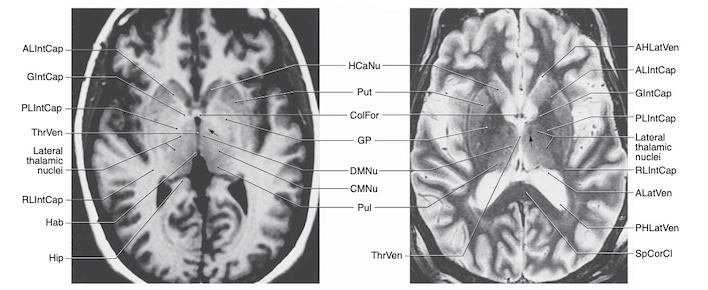

Bao trong nằm ở phần trong dưới của mỗi bán cầu. Trên thiết đồ cắt ngang não, bao trong có hình chữ V với đỉnh hướng vào trong.

Bao trong chứa các sợi phóng chiếu (chất trắng) quan trọng đi đến và đi từ vỏ não. Bao trong có thể được chia thành ba vùng khác nhau.

- Chi trước (anterior limb) nối vỏ não thuỳ trán với đồi thị và cầu não và các sợi đồi thị đến thuỳ trán.

- Gối/góc của bao trong (genu) chứa các sợi vận động vỏ não đi đến các nhân vận động ở thân não (corticobulbar fibers).

- Chi sau (posterior limb) chứa các sợi vận động từ thuỳ trán tạo thành bó vỏ gai (corticospinal tract) và các sợi cảm giác chiếu từ đồi thị đến thuỳ đỉnh của vỏ não. Chi sau cũng chứa các sợi thị giác và thính giác chiếu từ đồi thị đến thùy chẩm và thùy thái dương tương ứng.

CÁC HẠCH NỀN (BASAL GANGLIA)

Là các khối chất xám nằm trong chất trắng dưới các não thất bên. Do vị trí nằm ở đáy não (base) nên được gọi là hạch nền. Danh xưng hạch nền đôi lúc gây nhầm lẫn, tên đúng ra phải là các nhân nền (hạch là nhóm tế bào thần kinh ngoại biên, nhân là nhóm các tế bào thần kinh trung ương).

Các cấu trúc của hạch nền bao gồm nhân đuôi (caudate nucleus), bèo sẫm (putamen), cầu nhạt (globus pallidus), chất đen (substantia nigra, nằm ở não giữa), và nhân dưới đồi (subthalamic nuclei). Cầu nhạt và bèo sẫm tạo thành nhân bèo (lentiform nucleus), còn nhân đuôi và bèo sẫm được gọi là thể vân (striatum).

Nhân đuôi và bèo sẫm là các nhân nhận tín hiệu đầu vào chính của hạch nền, từ các vùng rộng của vỏ não mới, bao gồm cảm giác, vận động và các vùng liên hệ.

Cầu nhạt nằm ngay phía trong bèo sẫm và gồm hai phần (ngoài và trong). Chất đen (ở não giữa) và phần trong của cầu nhạt là các vùng đầu ra chính của hạch nền. Đầu ra tận cùng ở các vùng vỏ não trước trán, vùng vận động bổ sung và vùng tiền vận động qua trung gian đồi thị, để điều chỉnh tư thế và trương lực cơ, cũng như các vận động theo ý muốn và tự động.